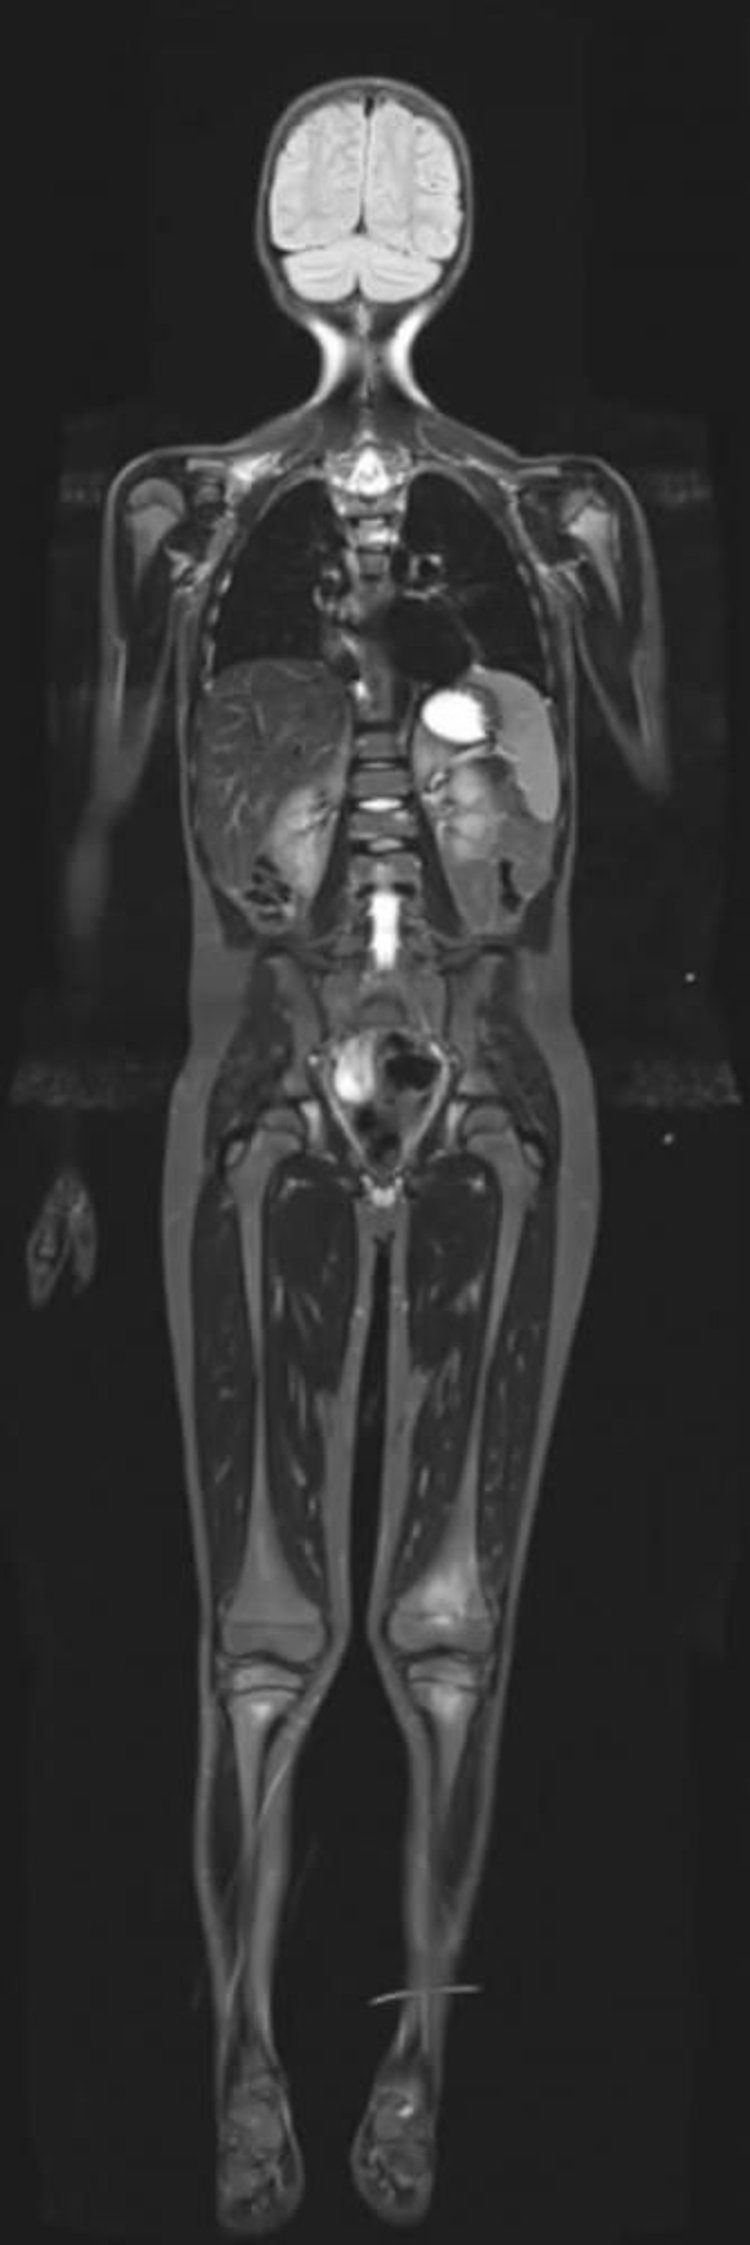

Short T1 Inversion Recovery MRI of the Whole Body

Short T1 inversion recovery MRI can suppress signals from fat allowing enhancement of other tissues with high water content.

Image courtesy of Hakan Ilaslan, MD.